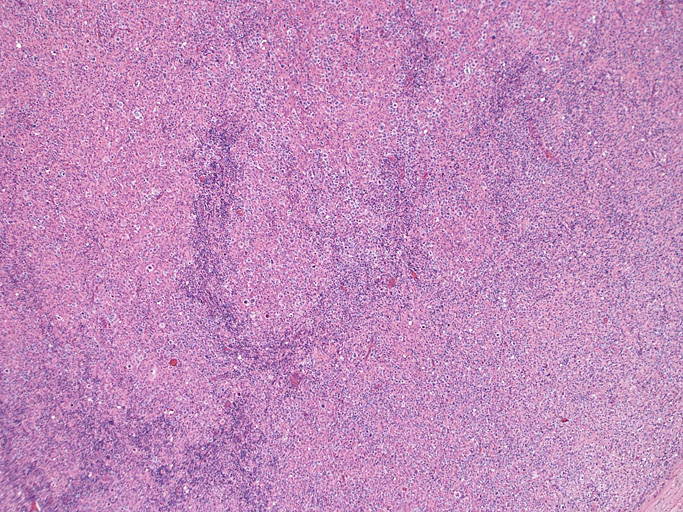

直径17mmの腫大したリンパ節。被膜は軽度線維性肥厚を示す。リンパ節の基本構造は失われ不明瞭な結節様構造が集蔟しているように見える。

光顕および免疫染色所見